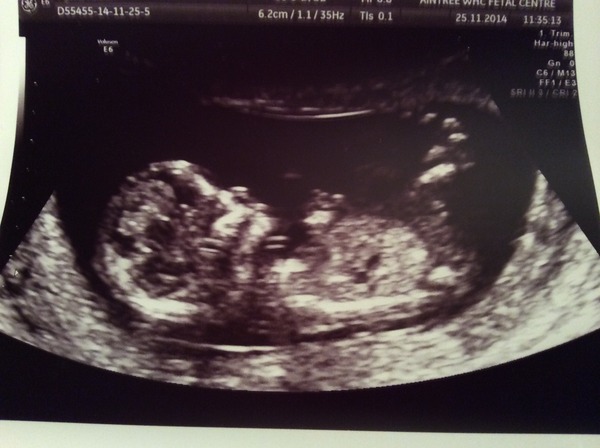

My 12 week scan. Any ideas, ladies?

hexy I'm clearly pants at this but I'm guessing girl.

Hexy, I will say boy for you.

I'd guess girl Hexy!